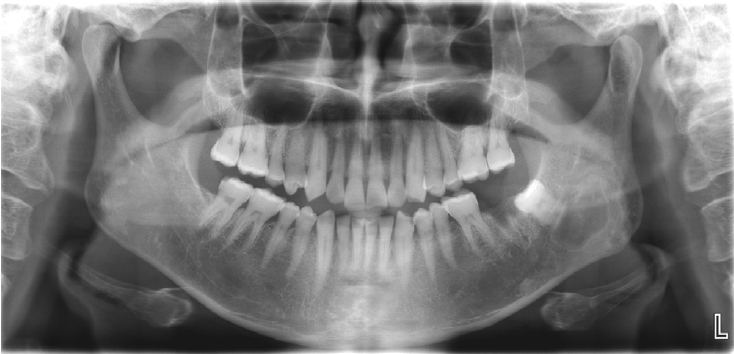

Intraosseous hibernoma of the mandible: A case report

Jin-Woo Han

J Korean Dent Assoc.

2025;63(10):335-339. Published online October 31, 2025